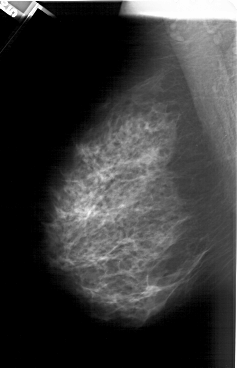

A_1374_1.LEFT_MLO

LEFT_MLO LINES 6241 PIXELS_PER_LINE 4021 BITS_PER_PIXEL 12 RESOLUTION 43.5 NON_OVERLAY